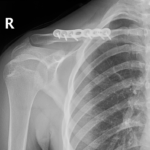

The surgeon in preparation for each surgery preconstructs a customized apparatus. Using wires or pins, the apparatus is surgically attached to the affected limb. Surgery is usually performed percutaneously through small incisions. Special care is taken to minimize injury to the bone and surrounding soft tissue, nerves and blood vessels when making specialized bone cuts.

During the adjustment phase the patient is followed up in the rooms every two weeks with clinical examination and x-rays. A close scrutiny is maintained to identify any complications early.

During the adjustment phase, the patient is followed up in the rooms every two weeks with clinical examination and x-rays. Close scrutiny is maintained to identify any complications early.